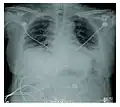

Rapid progression from initial symptoms to respiratory failure is a key feature. An X-ray that shows ARDS is necessary for diagnosis (fluid in the small air sacs (alveoli) in both lungs). In addition, a biopsy of the lung that shows organizing diffuse alveolar damage is required for diagnosis. This type of alveolar damage can be attributed to nonconcentrated and nonlocalized alveoli damage, marked alveolar septal edema with inflammatory cell infiltration, fibroblast proliferation, occasional hyaline membranes, and thickening of the alveolar walls. The septa are lined with atypical, hyperplastic type II pneumocytes, thus leading to the collapse of airspaces. Other diagnostic tests are useful in excluding other similar conditions, but history, X-ray, and biopsy are essential. These other tests may include basic blood work, blood cultures, and bronchoalveolar lavage.

Acute interstitial pneumonia showing a marked reduction in lung capacity -